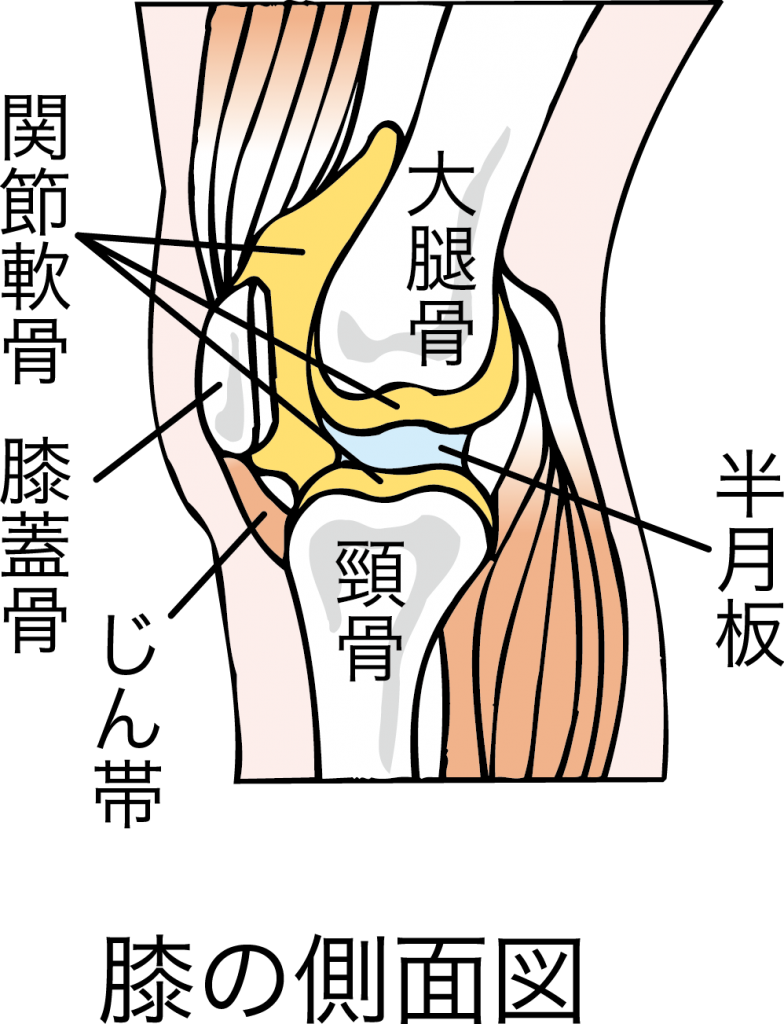

膝痛の方は必見 あぐらをかいた時に膝痛になる原因や対策を紹介 Healthing

ひざの雑学2 再生医療ナビ